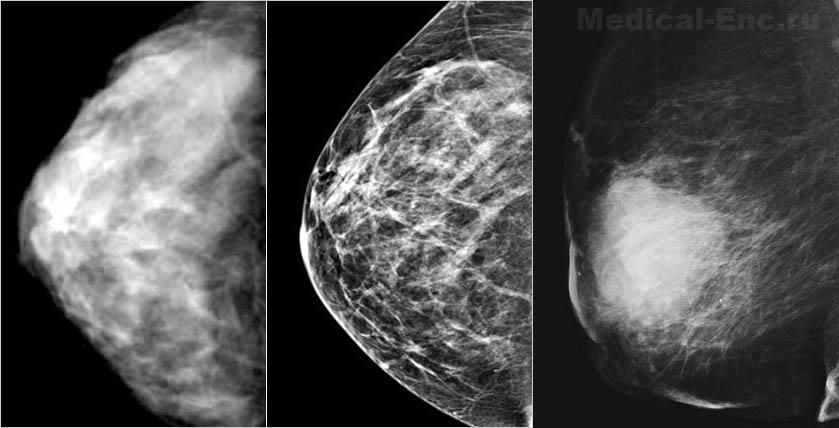

Мамографія - це рентгенографія молочної залози без застосування контрастних речовин. Незважаючи на появу контрастних методів рентгенологічного дослідження (дуктографія - дослідження проток залози і пневмомаммография - контрастування залози газом або повітрям), а також радіоізотопних досліджень молочної залози, мамографія до теперішнього часу залишається досить ефективним методом діагностики, особливо при розпізнаванні рака та інших пухлин молочної залози.

Мамографія має перед іншими методами дослідження ряд суттєвих переваг: 1) вона може бути виконана в будь-якому рентгенівському кабінеті і для неї практично немає протипоказань; 2) техніка мамографії відносно проста, необтяжлива для хворий і може бути здійснена в поліклінічних умовах; 3) променеве навантаження на хвору при правильній методиці і техніці дослідження відносно невелика, досягаючи на поверхні шкіри 0,3 р за один знімок, що при 4 рентгенограмах, зазвичай достатніх для судження про характер патологічних змін, не перевищує 1,2 р.